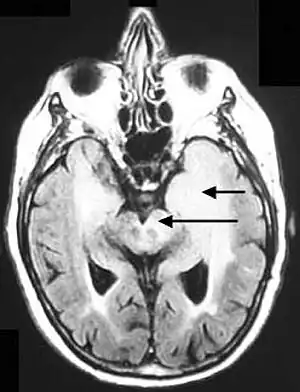

| Axial fluid-attenuated inversion recovery MRI image demonstrating tumor-related infiltration involving both temporal lobes (Short arrow), and the substantia nigra (Long arrow). | |